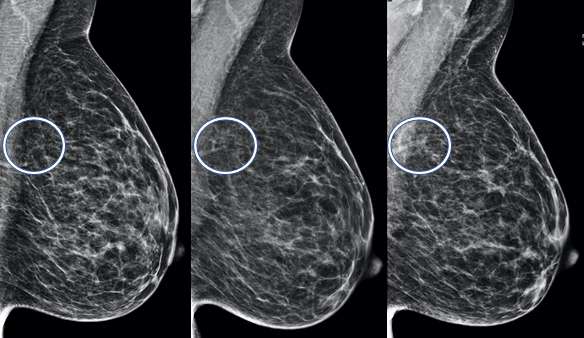

Global Asymmetry:

A global asymmetry is a finding seen on two projections of significantlyincreased breast tissue occupying greater than one quadrant. Global asymmetries that have been evaluated without suspicious features are most lynormal variantsand do not require additional follow up.

Implant displaced MLO and CC views of the breast demonstrate increased density through the left breast, consistent with a global asymmetry.